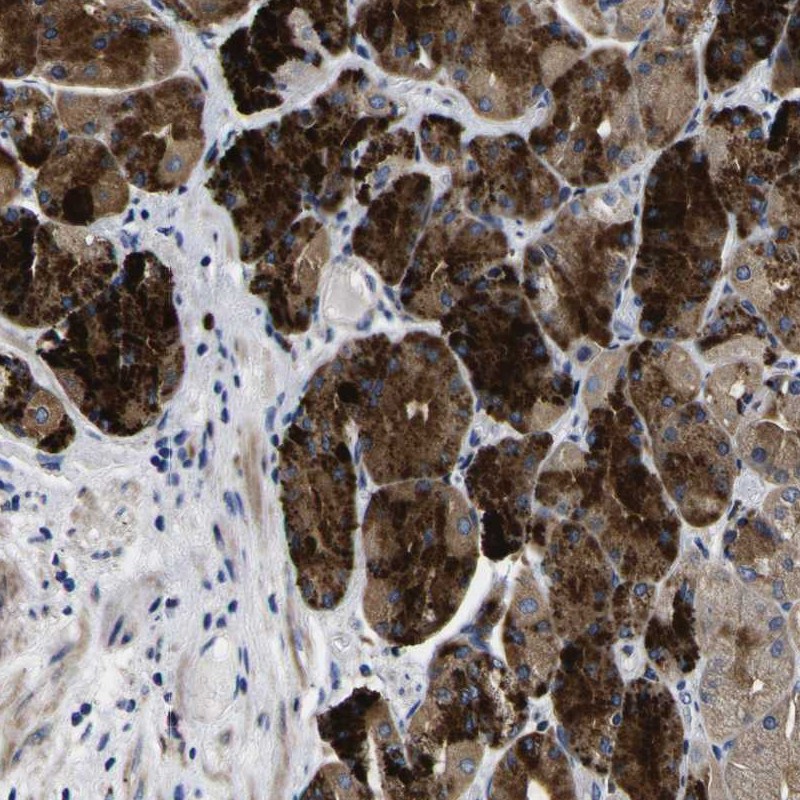

Immunohistochemical staining of human stomach shows strong cytoplasmic positivity in granular pattern in glandular cells.